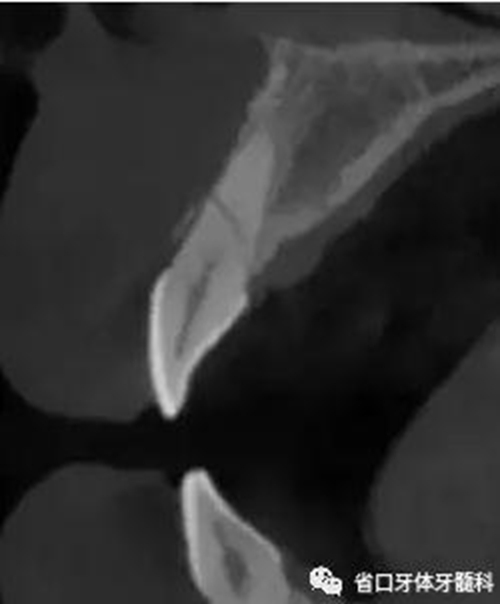

圖4:21術(shù)前

CBCT:11、21頸部以下均見(jiàn)一完全性折裂線,兩牙折裂線均位于頜骨內(nèi)且斷端移位不明顯,相應(yīng)唇側(cè)骨板亦見(jiàn)斷裂且輕度移位。